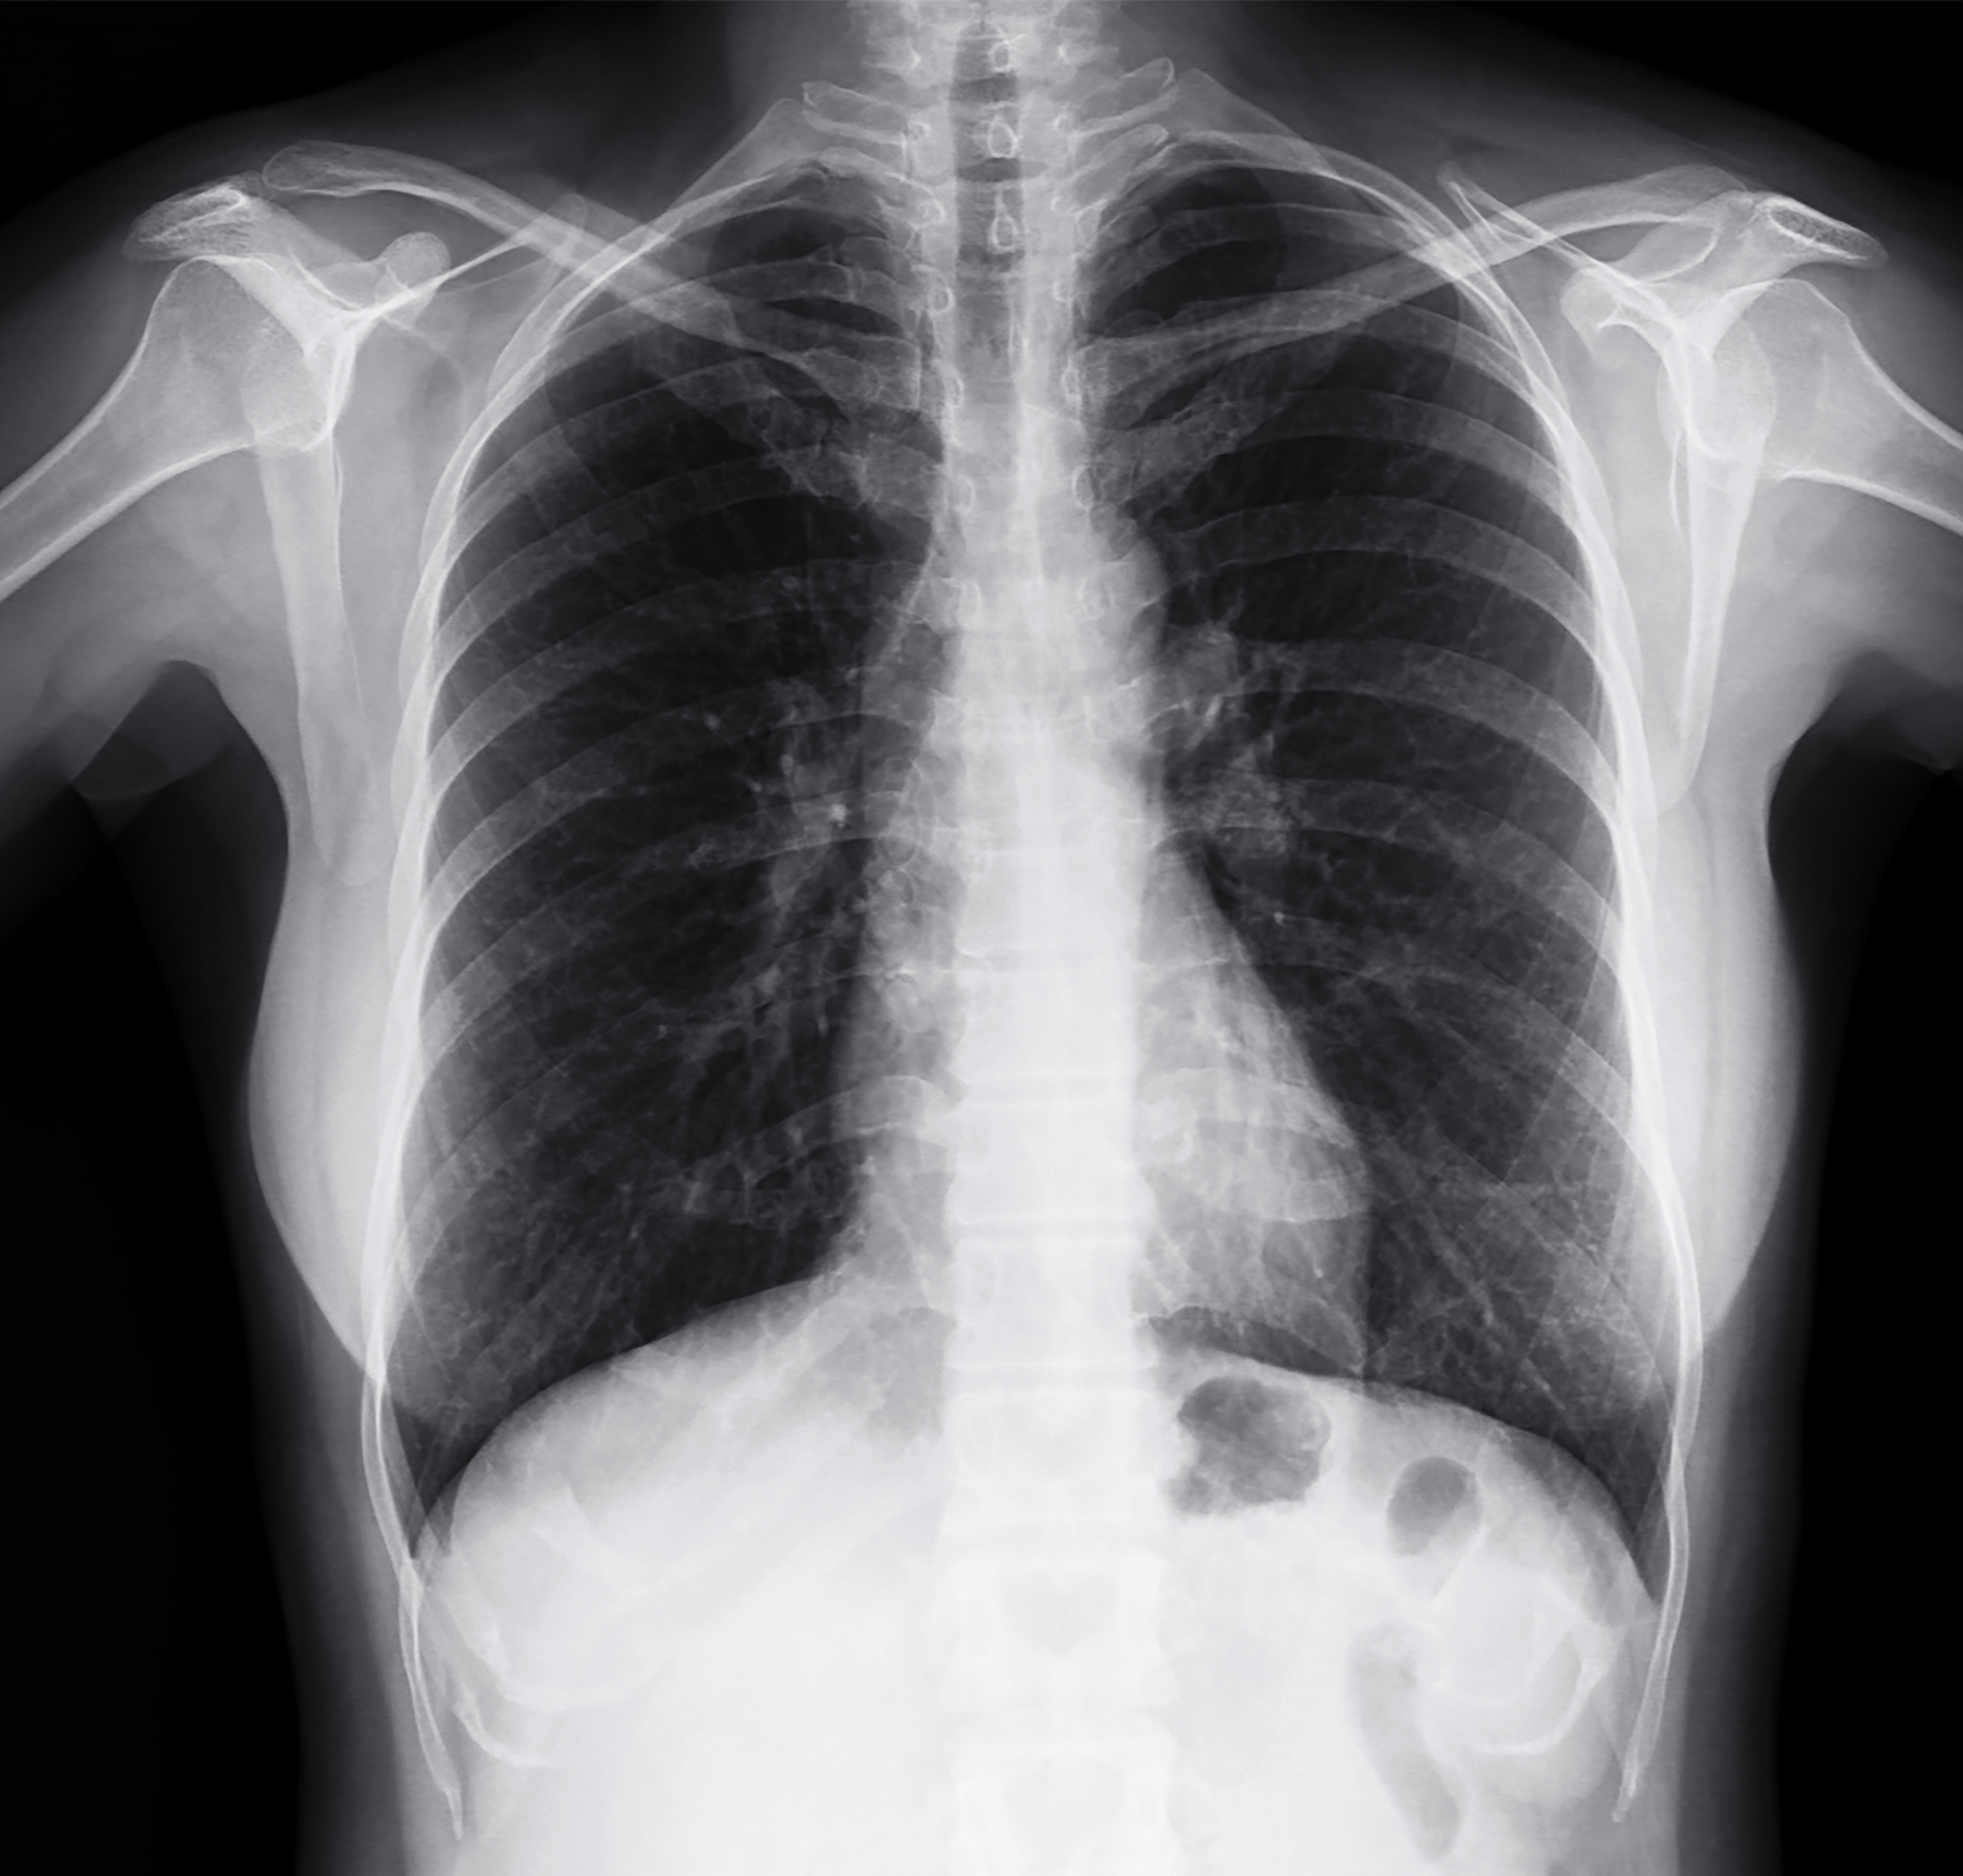

Inhalation |

| Many chemicals and other hazardous substances release fumes, vapours or tiny particulates.

Breathing these can cause severe respiratory problems. |